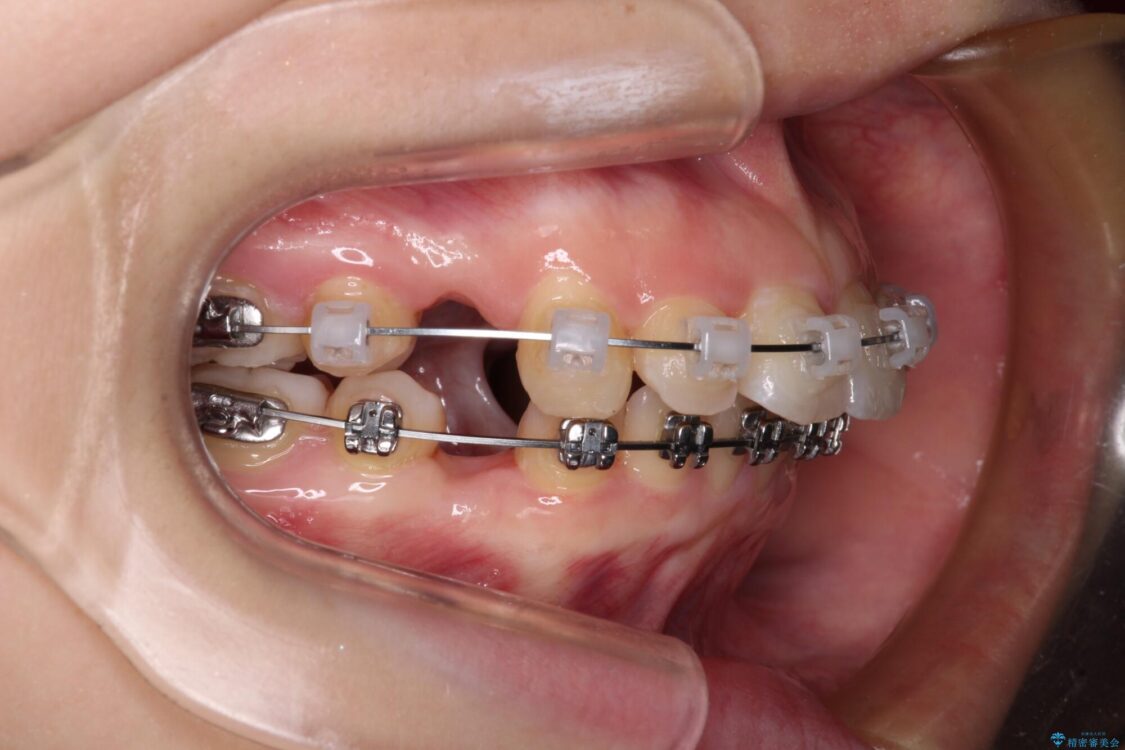

治療途中

• 【モニター】口が閉じられない ワイヤー装置での抜歯矯正 治療途中画像

※写真にある上顎装置はメタルブラケットではありません。メーカー在庫都合などにより別の装置を使用しております。

舌の突出癖により、前突になったと考えられたため、舌のトレーニングをしっかりと行うよう指導しました。